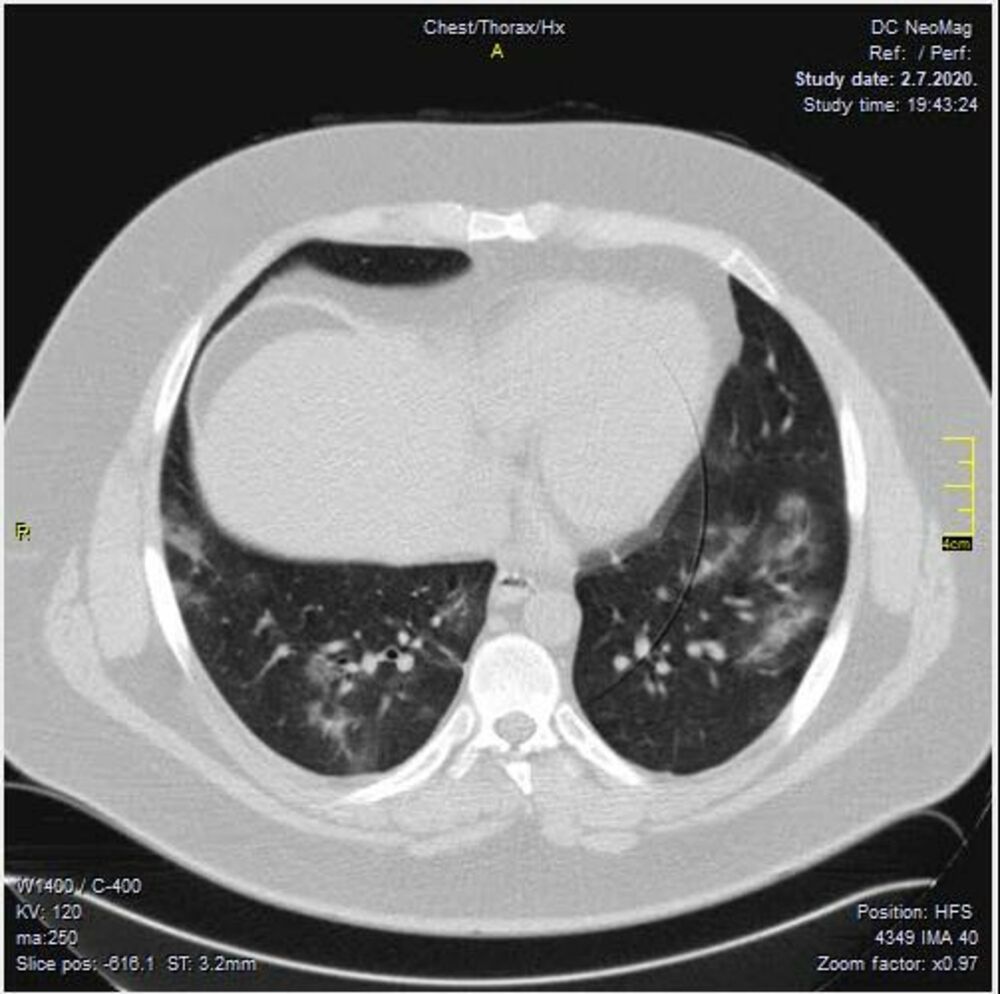

Krenulo je sa divljim sojem. Znamo da je i on imao svoje varijante. Ono što je bilo u samom početku kod nas je ličilo na samu osnovu.

Kada se pogleda pažljivo i deluje divlje, nema neke pravilnosti.

Neki međusoj je bio u leto 2020.

Ono što je karakteristično je to da su ovo nalazi koji su 2. i 3. dana bolesti u I fazi. Znači ne u progresivnoj, već u uvodnoj fazi kada uglavnom nema CT znaka. Fibrozne trake već drugog dana???? Ground glass oko većih grana bronha. Kao da bolest ne može da sačeka, kao da klija gde stigne.